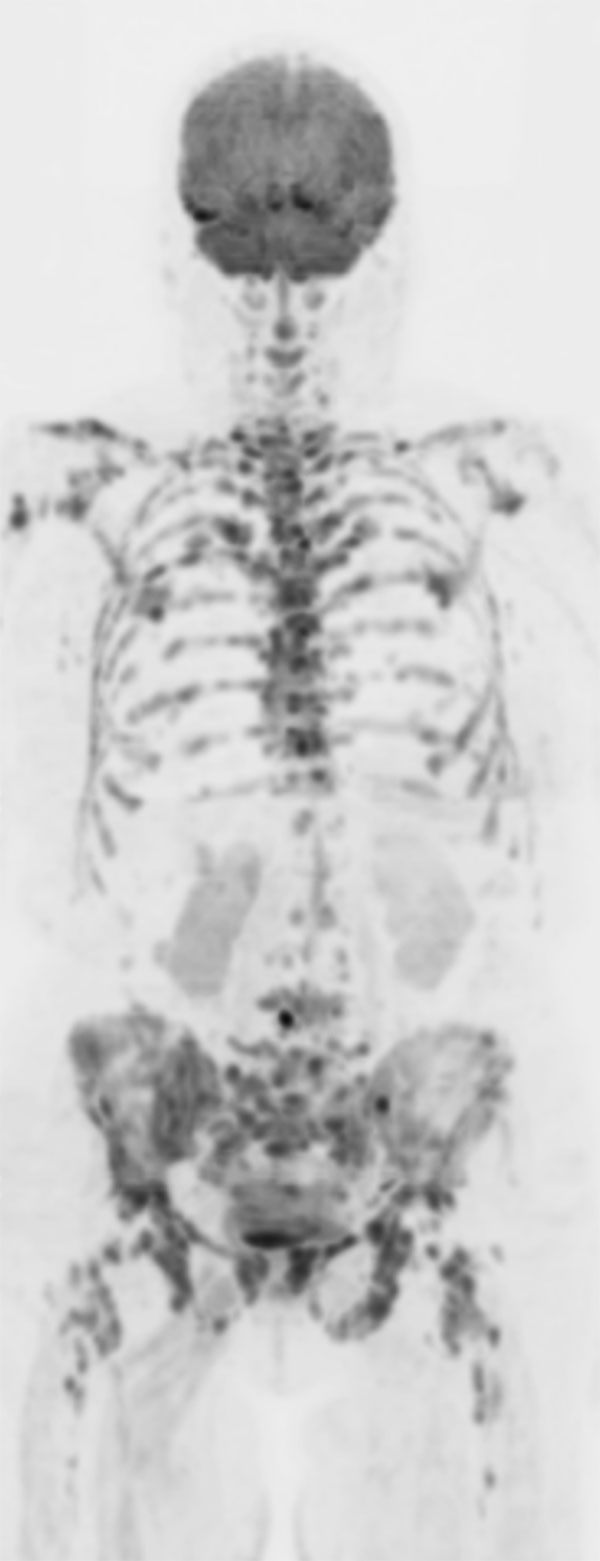

Patient with bone lesions.